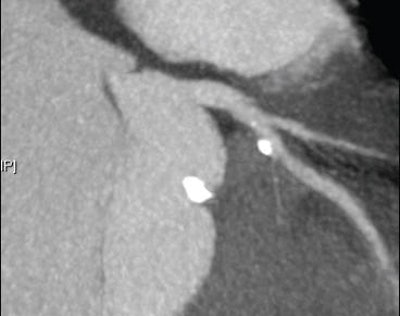

![]() |

| Top, triple or multirule-out CTA in a patient with atypical pain but normal arteries shows good opacification in all three arterial beds (coronary, pulmonary, aorta). Below, CTA of a low-risk patient with chest pain shows typical "vulnerable plaque" with little stenosis and positive remodeling. Bottom, triple rule-out scan in a patient presenting with atypical chest pain reveals aortic dissection. |